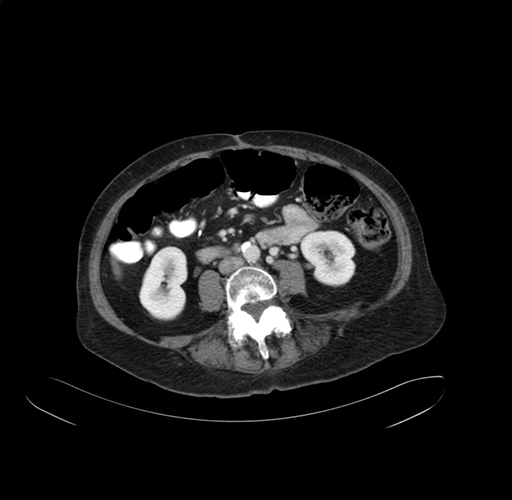

Pre-Chemo: Axial Venous

Axial Venous